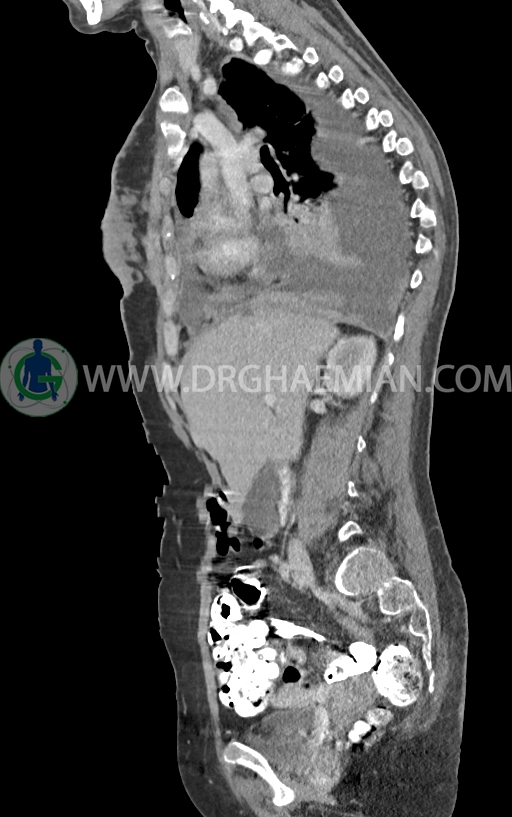

در سی تی اسکن اسپیرال ریه و مدیاستن -شکم و لگن با کنتراست خوراکی و وریدی (مولتی دیدکتور 16 با مقاطع ظریف و بازسازی های ساژیتال و کرونال) :

–ضایعات استخوانی لیتیک فراوان منتشر در تمامی طول ستون مهره و لگن رویت شدند که مطرح کننده متاستاز استخوانی می باشند.

–شکستگی پاتولوژیک در مهره های T6 , T10 , T11

–کیفوز موضعی در Level T10 , T11 در ستون مهره

–رتروپالشن شکستگی مهره T10 همراه با ایجاد تنگی کانال نخاعی

–ضایعه استخوانی لیتیک کوچک همراه با شکستگی در قوس خلفی دنده 11 راست (متاستاز استخوانی)

–متاستاز استخوانی در قوس خلفی دنده 8 راست

–خط لوسنت مشکوک برای شکستگی در قوس خلفی دنده 8 راست و قوس خلفی دنده 7 چپ

مشهود است.